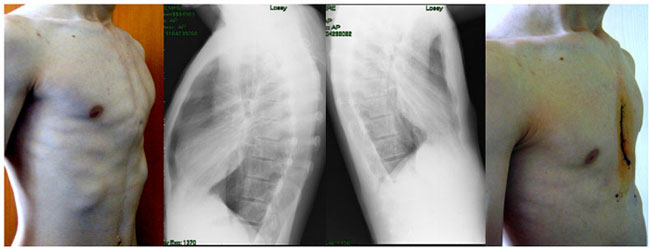

Pektus ekskavatum deformitesinin cerrahi tedavisinde 1949'da Ravitch, hala modifiye olarak pek çok merkezde uygulanmakta olan düzeltme tekniğini tanımlamıştır.

Bu teknikte deformiteyi oluşturan tüm kıkırdak kostaların perikondriyumları ile beraber eksize edilir, ksifoid ve interkostal kas lifleri de sternumdan ayrılır, manubrium seviyesinde yapılan transvers osteotomiyle sternum öne doğru kırılarak şekillendirilir. Bu teknik Kirschner teli veya kısa bir çelik bar ile sternumun öne doğru yer değiştirmesine izin verir. Ravitch tekniğinin modifiye formunda ise kıkırdak kostalar perikondrial kılıflar yerinde bırakılarak rezeke edilir, interkostal kas lifleri de kesilmez.

Bu teknik hem pektus ekskavatum hem pektus karinatum deformitelerinin tedavisinde uygulanabilir.